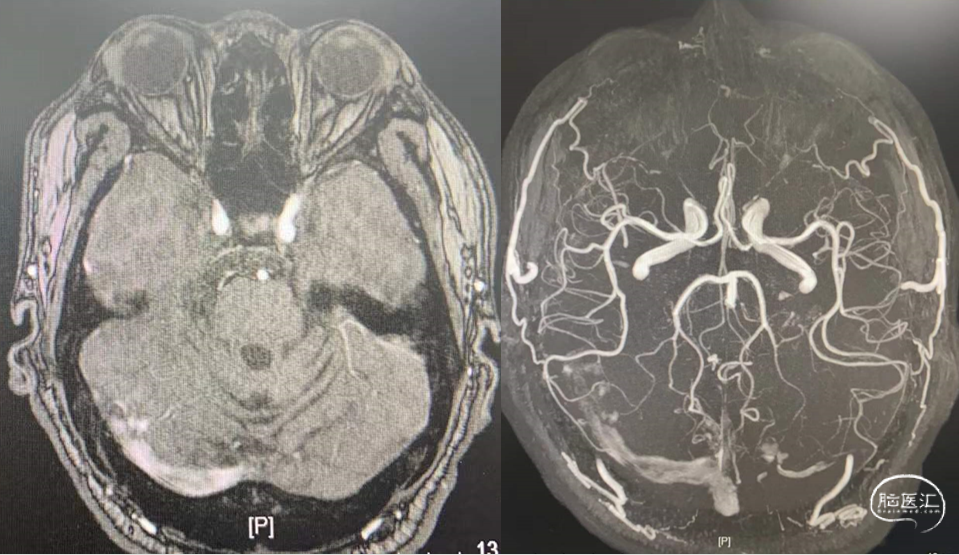

头颅MRV(2022-1-5)

头颅核磁:可见横窦高密度

影 像

脑静脉窦血栓(上矢状窦、右侧横窦、乙状窦)